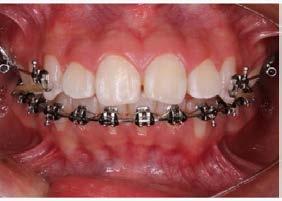

Manejo interceptivo de maloclusión clase II esqueletal

Manejo interceptivo de maloclusión clase II esqueletal con remanente de crecimiento: reporte de un caso clínico

Introducción: La maloclusión clase II provoca proporciones irregulares en el perfil facial. Puede deberse a un maxilar adelantado y a incisivos superiores proinclinados y protruidos. Esta condición puede corregirse mediante el uso de aparatos ortopédicos en pacientes en crecimiento.

Objetivos: Conseguir clase I canina, controlar el crecimiento vertical, disminuir la convexidad esqueletal, reducir la sobremordida horizontal y mejorar el perfil facial. Caso clínico: Paciente femenina de 9 años, clase II esqueletal, biotipo dolicofacial, perfil convexo, clase II molar, clase II canina y proinclinación de incisivos superiores e inferiores. Resultados: Se logró clase I canina, se controló el crecimiento vertical, se redujo la convexidad esqueletal, se mejoró la sobremordida horizontal y el perfil facial. Conclusiones: El uso combinado de aparatos ortopédicos y aparatología fija en pacientes en crecimiento, junto con un diagnóstico y plan de tratamiento acertado, permite obtener resultados exitosos y estables en la corrección de estas maloclusiones.

Palabras clave: arco extraoral, clase II, ortopedia, cantilever, crecimiento.

La relación maxilomandibular desempeña un papel importante en la posición de los molares y puede clasificarse como clase I, II o III, de acuerdo con la clasificación de Angle. Esqueletalmente, esta relación solo puede determinarse mediante estudios radiológicos; los modelos de estudio solo ofrecen una aproximación clínica.1